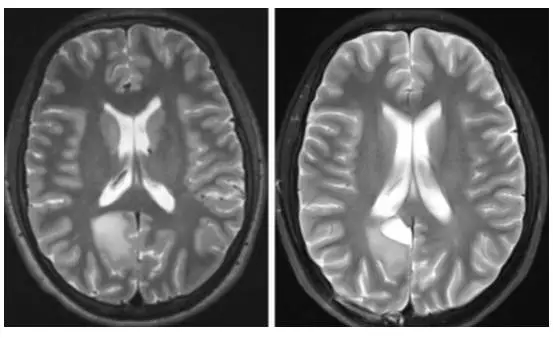

图2. 在术者工作生涯的早期,术者采用同侧经纵裂入路处理房部内侧的低级别胶质瘤。受限于肿瘤外侧面的操作角度,仅对肿瘤进行了部分切除。通过回顾该病例,萌生了PITTA的雏形。

图3. 房部内侧壁和三角区的胶质瘤(左上图),脑膜瘤(左下图)和动静脉畸形(右图),均可采用PITTA入路(包括术后影像)。